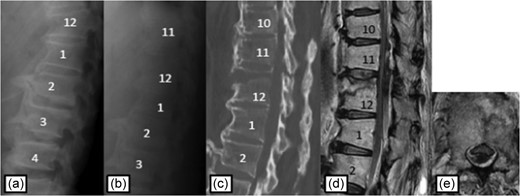

Plain radiographs on initial assessment (a) and on admission (b); Sagittal CT image (c) showing the hyperextension fracture at T12; MRI T2-weighted image (d, e) showing the epidural hematoma compressing the dura matter.